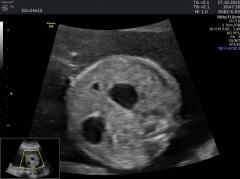

@diagnóstico 96

Se presenta el caso de una paciente de 39 años de edad, primigesta, sin antecedentes personales ni familiares de relevancia. La paciente adjunta el estudio de screening de aneuploidías de la semana 11-14, que arroja bajo riesgo. Las imágenes que… Ver más.